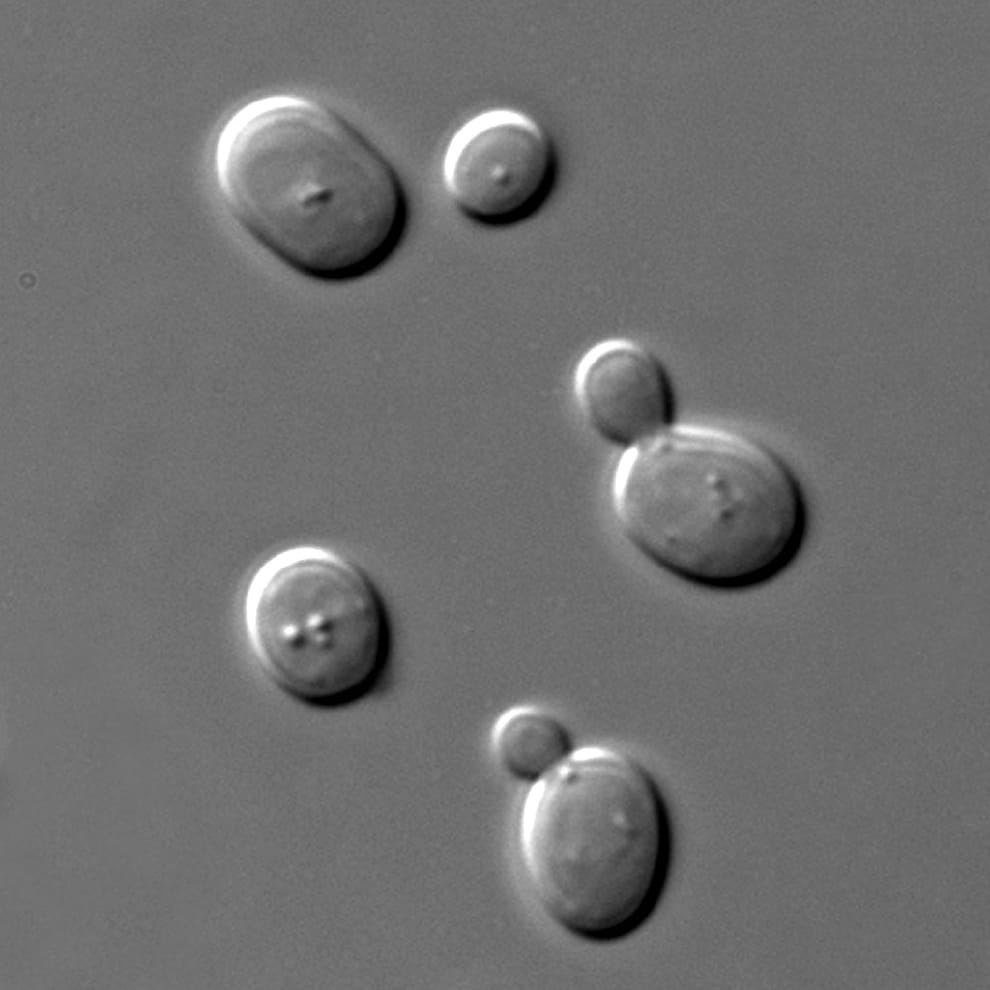

文章插圖

在男子體內發現的釀酒酵母俗稱「啤酒酵母」、「麵包酵母」,它能幫助醣類發酵的特性常被用在釀酒和烘焙上。圖為顯微鏡下的釀酒酵母。